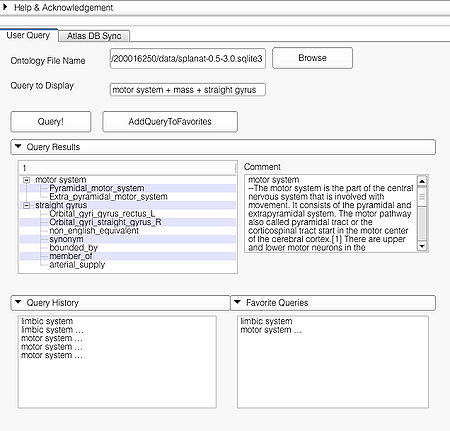

This page is useful for creating visualizations based on user typed queries. The user inputs consist of the Ontology File Name and Query To Display. The button Query fires a query and causes the module to start processing the user query for visualization. The button AddQueryToFavorites adds the last typed user query to the list of favorite queries. The favorite query list is shown in the bottom panel Favorite Queries. Additionally, the interface also shows a history of typed queries in the panel Query History.

The Query Results panel shows the result of a query, consisting of all the associated predicates and parts for the query. The Figure User Page GUI shows the result of a simple query "limbic system".Additionally, the interface also shows a Comment that contains any relevant textual information about the query obtained from the ontology. The user can refine a search by selecting from the query result. Optionally, the user can also select by clicking on any selection from the Query History or Favorite Queries panel to redo search and visualization. The interface supports the multiple selections to form complex queries. The visualization resulting by searching with the query "Limbic system" is shown below.

A complex query contains two or more simple or specialized queries. A complex query is typically specified by using a "+". Note that the "+" does not signify an ANDing of the search terms. Instead each string separated by the "+" is searched as an individual query in the ontology. The result of using a complex query is shown below. The Application interface shows the results for all the terms that are matched in the ontology (i.e. the motor system and straight gyrus.) Unmatched terms such as the user added models (e.g. mass) are only displayed. The figure shows an example of a complex query comprised of simple queries.

Specialized queries can be combined with other simple or specialized queries to form complex queries (e.g. "motor system + straight gyrus;synonym"). An example of a complex query using specialized and simple query terms is shown below.